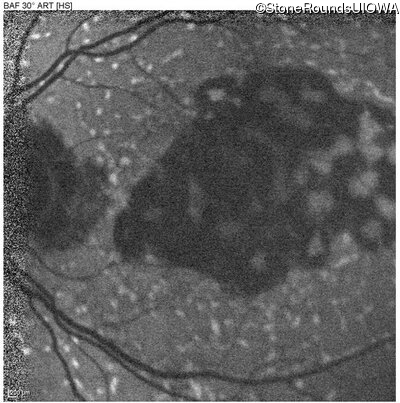

AR Stargardt Disease (IIA)

Age at visit: 59 years

This 59 year old man has noticed some blank spots near the center of his vision over the last 2 years.

Diagnosis & molecular findings

Disease Gene Allele 1 variant(s) Allele 2 variant(s) Inheritance mode

AR Stargardt Disease ABCA4 Leu2027Phe CTC>TTC IVS30+1321 A>G AR